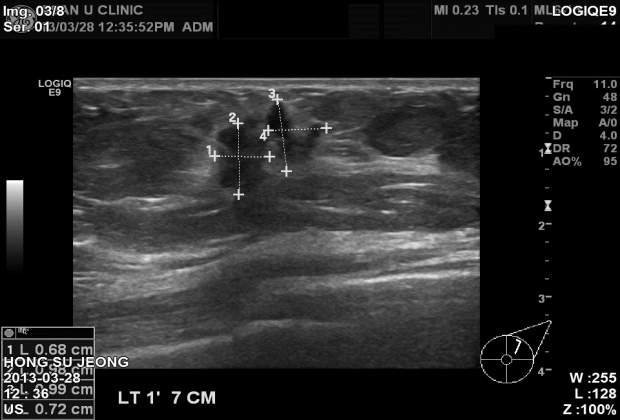

아산유외과 개원 후 1번째 유방암 진단.

목욕하다 잡자기 잡히는 좌측유방에 혹이 있어 내원하신 70세 환자분입니다.

만져지는 혹이 있었지만 통증은 전혀없으셔서 머뭇거리시다

검진을 하시게 되었습니다.